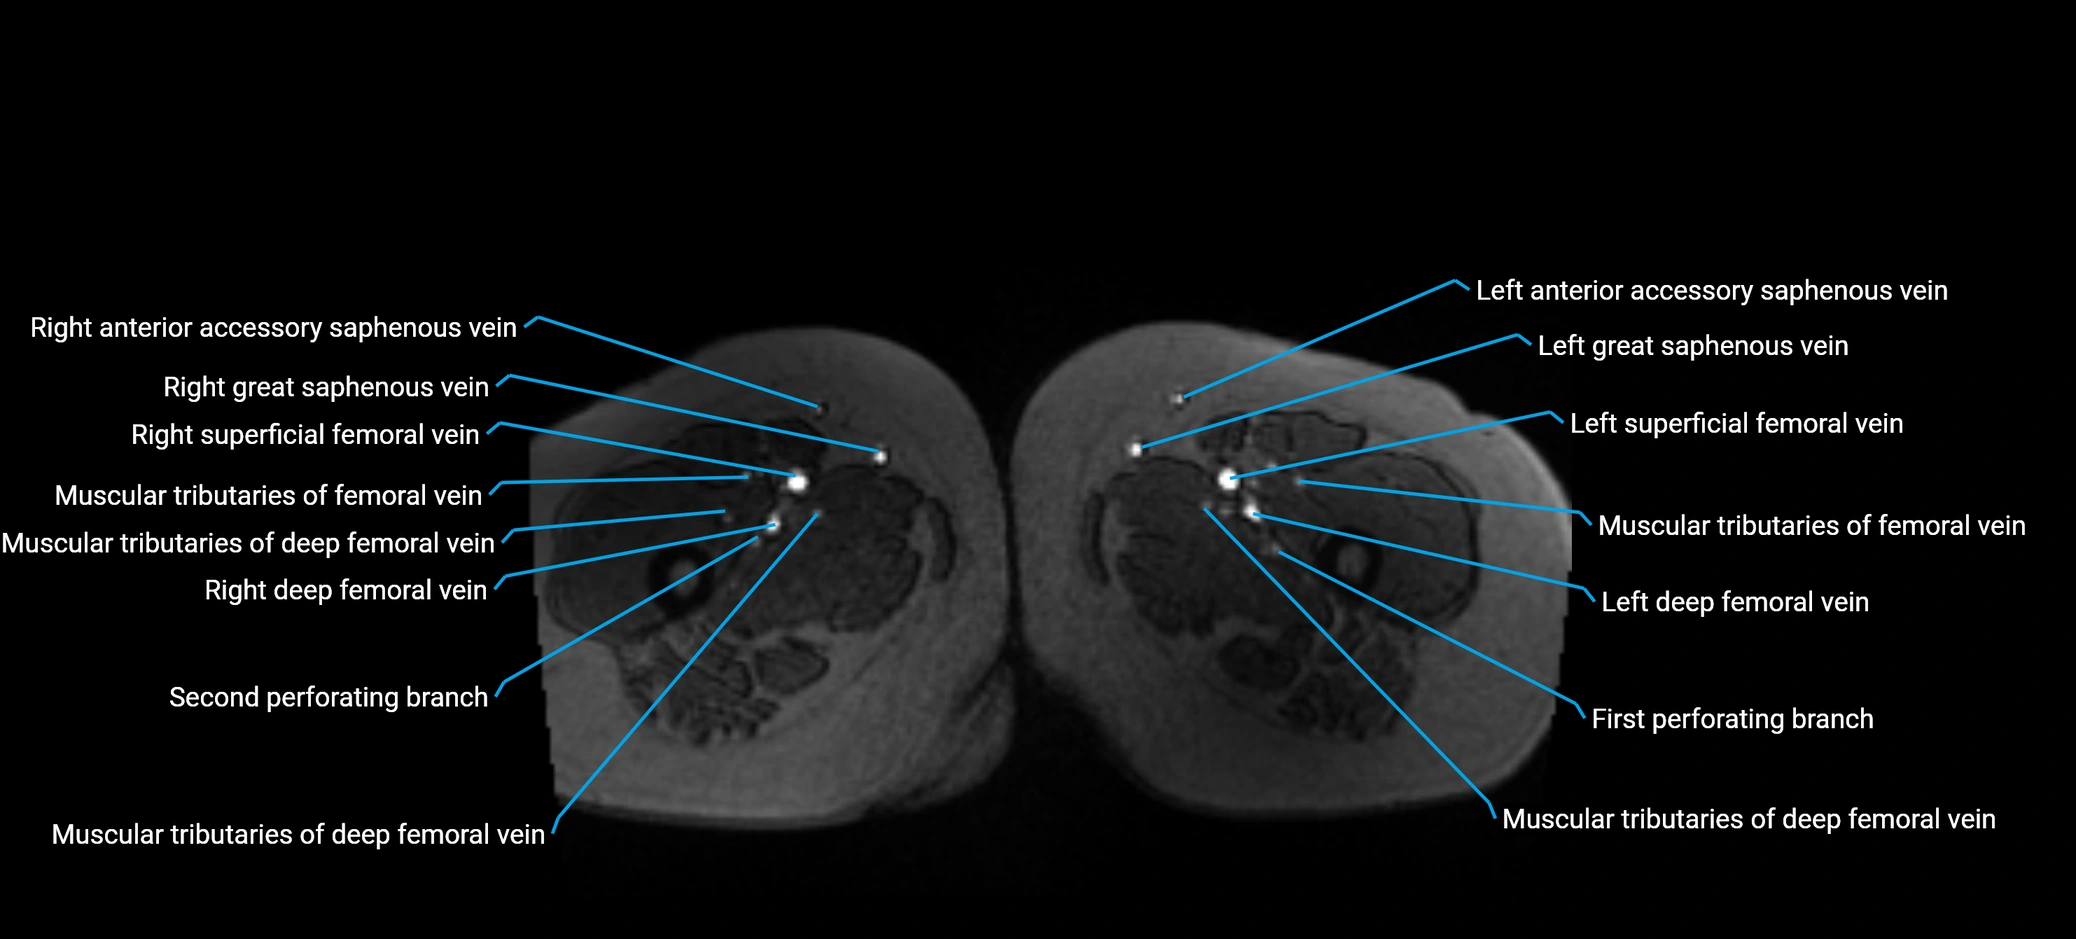

MRI image

image